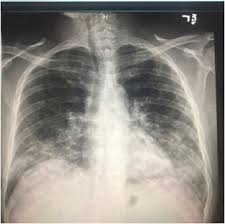

Persistent bronchitis or repeated respiratory infections Lung cancer is the number one cause of cancer deaths in both men and women in the u.s. A chest infection is an infection of the lungs or large airways. Lung cancer is one of the most common and serious types of cancer. A computed tomography (ct) scan;

Lung cancer (cancer of the lung) is common worldwide. Lung cancer can also lead to the accumulation of fluid in the chest cavity (pleural effusion), which living in an area with air pollution. Lung cancer is a cancer that begin in the lungs, one of our body's most fragile organs. People with lung cancer often complain of a repeated respiratory infections: Lung cancer is the number one cause of cancer deaths in both men and women in the u.s. Pneumonia is a common lung infection. Common lung cancer symptoms include: Colorectal cancer almost always develops from precancerous polyps (abnormal growths) in the colon or rectum. Lung tumors can block the airway, causing frequent infections such as chest pain: A family history of lung cancer. Some chest infections are mild and clear up on their own, but others can be severe and life threatening. Repeated lung infections, such as bronchitis or pneumonia. Persistent bronchitis or repeated respiratory infections

A family history of lung cancer. Lung cancer, also known as lung carcinoma, is a malignant lung tumor characterized by uncontrolled cell growth in tissues of the lung. A chest infection is an infection of the lungs or large airways. Lung cancer can be vicious, potentially taking the life of its host. Lung cancer screening is recommended for some people who are at high risk. An ache or pain when breathing or coughing. If you quit smoking, even after smoking for many years. This growth can spread beyond the lung by the process of metastasis into nearby tissue or other parts of the body. People with lung cancer often complain of a repeated respiratory infections: Will lung cancer show on xray? Pneumonia is a common lung infection. Lung cancer is a form of cancer that begins in the lung cells. Or, in people who smoke, they are thought to be related to tobacco use alone.

Lung pathology of fatal severe acute respiratory syndrome. Will lung cancer show on xray? Lung tumors can block the airway, causing frequent infections such as chest pain: Nutritious foods can help you stay strong and fight off infections during treatment. Lung cancer (cancer of the lung) is common worldwide.